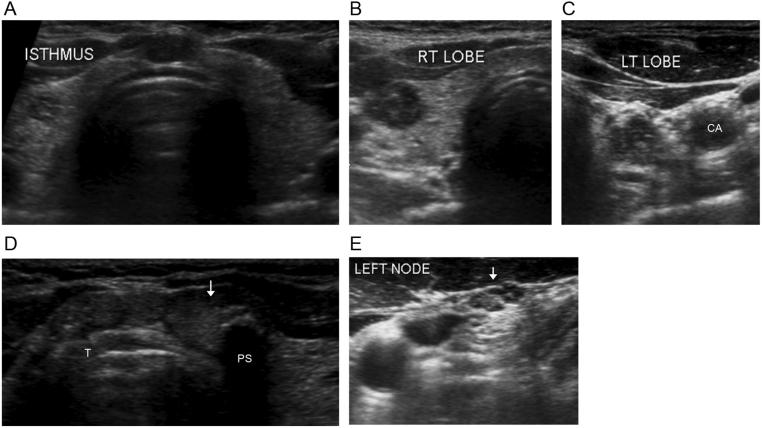

Multifocal papillary thyroid carcinoma (PTC) is common and the number of tumor foci rarely exceeds ten. The mechanism of multifocal disease is debated, with the two main hypotheses consisting of either intrathyroidal metastatic spread from a single tumor or independent multicentric tumorigenesis from distinct progenitor cells. We report the case of a 46-year-old woman who underwent total thyroidectomy and left central neck lymph node dissection after fine-needle aspiration of bilateral thyroid nodules that yielded cytological findings consistent with PTC. Final pathology of the surgical specimen showed an isthmic dominant 1.5 cm classical PTC and over 30 foci of microcarcinoma, which displayed decreasing density with increasing distance from the central lesion. Furthermore, all malignant tumors and lymph nodes harbored the activating BRAF V600E mutation. The present case highlights various pathological features that support a mechanism of intraglandular spread, namely a strategic isthmic location of the primary tumor, radial pattern of distribution and extensive number of small malignant foci and BRAF mutational homogeneity. Learning points: Multifocal papillary thyroid carcinoma (PTC) is commonly seen in clinical practice, but the number of malignant foci is usually limited to ten or less. There is no clear consensus in the literature as to whether multifocal PTC arises from a single or multiple distinct tumor progenitor cells. Strategic location of the dominant tumor in the thyroid isthmus may favor intraglandular dissemination of malignant cells by means of the extensive lymphatic network. An important pathological finding that may be suggestive of intrathyroidal metastatic spread is a central pattern of distribution with a reduction in the density of satellite lesions with increasing distance from the dominant focus. PTCs originating from the isthmus with intraglandular metastatic dissemination behave more aggressively. As such, a more aggressive treatment course may be warranted, particularly with regard to the extent of surgery.

A thyroid gland with over 30 foci of papillary thyroid carcinoma with activating BRAF V600E mutation.